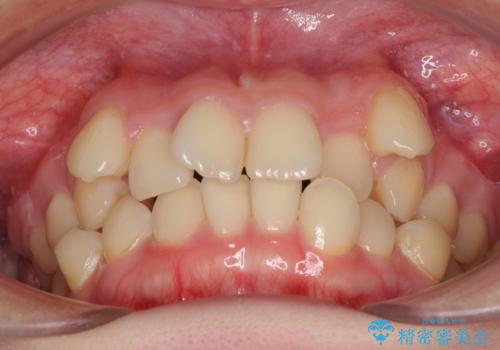

上顎の八重歯と下顎前歯の欠損 ワイヤー装置による抜歯矯正

- 上顎の八重歯を気にして来院された患者様です。

診察したところ、下顎前歯が2本欠損していたため、上下のバランスを取りながら八重歯を改善するため、上顎左右第一小臼歯2本を抜歯することとしました。

下顎前歯と本来抜歯矯正で抜歯する歯とは大きさが異なるため、仕上がりの咬み合わせは理想的なものとはなりませんでしたが、気になっていた八重歯はきれいに改善することができました。